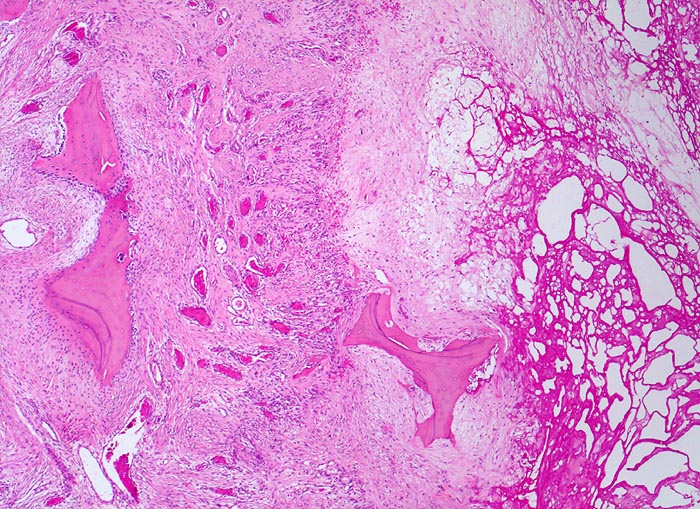

Coxarthrose: Geröllzyste

Randbereich einer Geröllzyste. Im Zentrum der Zyste nekrotischer Detritus und partiell resorbiertes avitales Knochenbälkchen. Die Geröllzyste wird umgeben von einem gefässreichen Granulationsgewebssaum. Darin liegt ein Knochenbälkchen, welches zystenwärts eine gesteigerte Resorption und auf der zystenabgewandten Seite einen gesteigerten Anbau mit Ausbildung einer Osteoblastentapete zeigt.

74-jährige leicht adipöse Patientin mit Anlaufschmerz, belastungsabhängigem Schmerz und zunehmender Versteifung im Hüftgelenk. Im Röntgenbild des Hüftgelenks zeigen sich eine Gelenkspaltverschmälerung, subchondrale Osteolysen, Usuren und randständige Osteophyten.